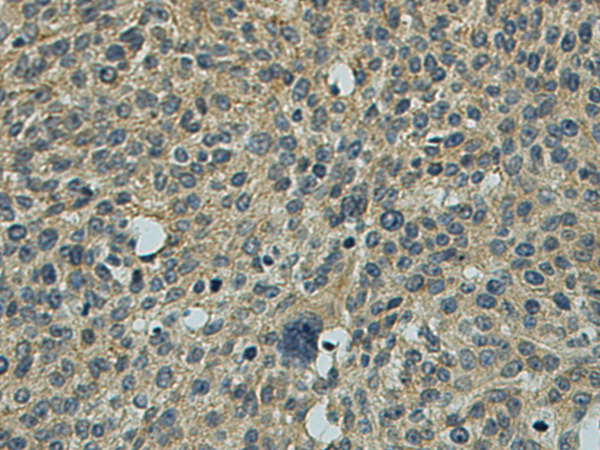

分类: 科研抗体货号: P09848别名: L11; HN1L; C16orf34应用: IHC反应种属: Human